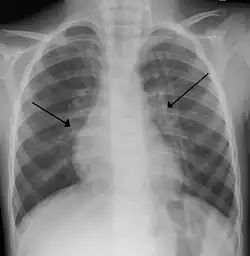

Diagnosis

The diagnosis is typically made by a provider through clinical history and physical exam. Chest X-ray is sometimes useful to exclude bacterial pneumonia, but not indicated in routine cases.[1] Chest x-ray may also be useful in people with impending respiratory failure.[15] Additional testing such as blood cultures, complete blood count, and electrolyte analyses are not recommended for routine use although may be useful in children with multiple comorbidities or signs of sepsis or pneumonia.[8][15] Electrolyte analyses may be performed if there is concern for dehydration.[1]